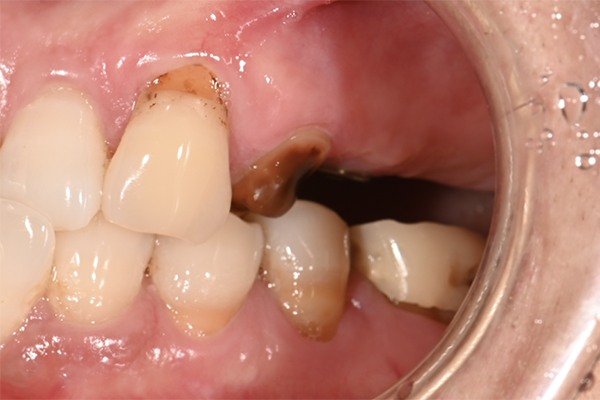

| 主訴 | 右下の奥歯が痛い |

|---|---|

| 治療内容 | 右下奥歯が割れていたため抜歯、その後インプラント治療を行った。(左の写真は抜歯後の写真) |

| 治療期間 | 4ヶ月 |

| 治療費 | 41万5千円 |

| 治療 リスク | 抜歯後インプラントの処置まで3ヶ月程度治癒期間(骨ができるまでの期間)が必要なことがあります。 |